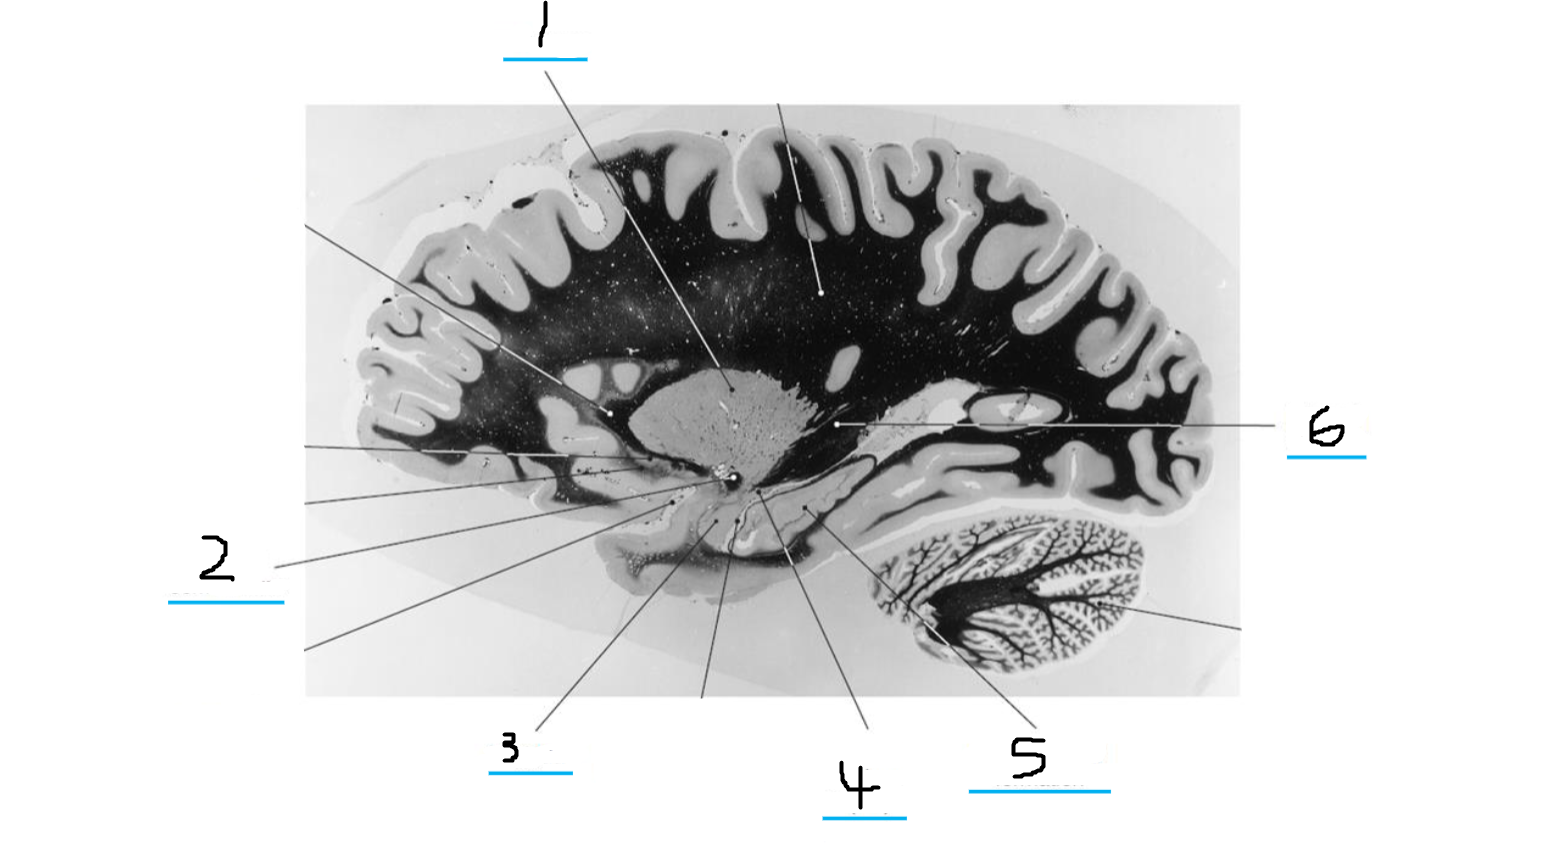

#1 is the:

Cingulate Gyrus

#2 is the:

Septum Pellucidum

#3 is the:

Lateral Ventricle

#4, #7, and #12 is the:

Fornix

#5 is the:

Third Ventricle

#6 is the:

Anterior Commissure

#8 and #11 is the:

Amygdala

#9 is the:

Hypothalamus

#10 is the:

Mammillary Body

#13 is the:

Insula

#14 is the:

Globus Pallidus

#15 is the:

Putamen

#16 is the:

Internal Capsule

#17 is the:

Caudate

#18 is the:

Corpus Callosum